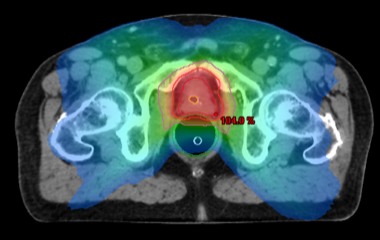

Par contre, les cancers de risques intermédiaires et élevés peuvent évoluer plus rapidement et un traitement radical sera nécessaire, soit par une exérèse chirurgicale (prostatectomie radicale totale), soit par une radiothérapie interne (curiethérapie) ou externe. Dans notre centre, l’intégration de l’imagerie multimodale (Scanner ou Résonance magnétique nucléaire) au processus de planification de la radiothérapie ainsi que la technique d’irradiation par modulation d’intensité (IMRT) permettent guider les rayons vers la tumeur de façon extrêmement précise, ce qui accroît l’efficacité du traitement tout en évitant d’endommager les tissus sains avoisinants.

Répartition des doses de radiothérapie administrées sur la prostate et épargne des tissus avoisinants:

doses de radiothérapie administrées sur la prostate.png